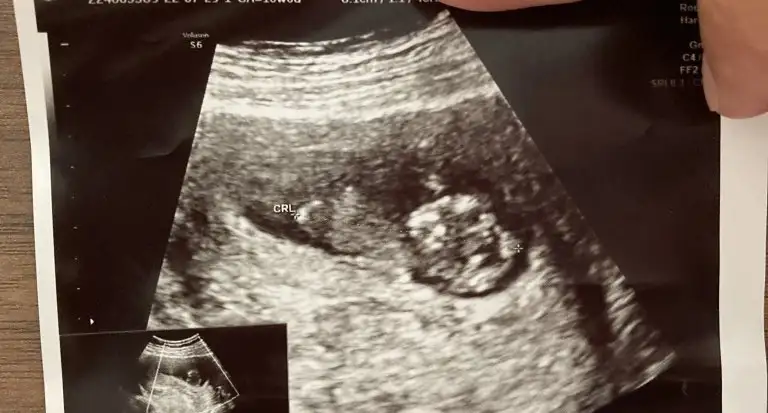

10 haftalık tahmin alabilirmiyiz

• IMG-20220730-WA0006.webp

50,1 KB · Görüntüleme: 45